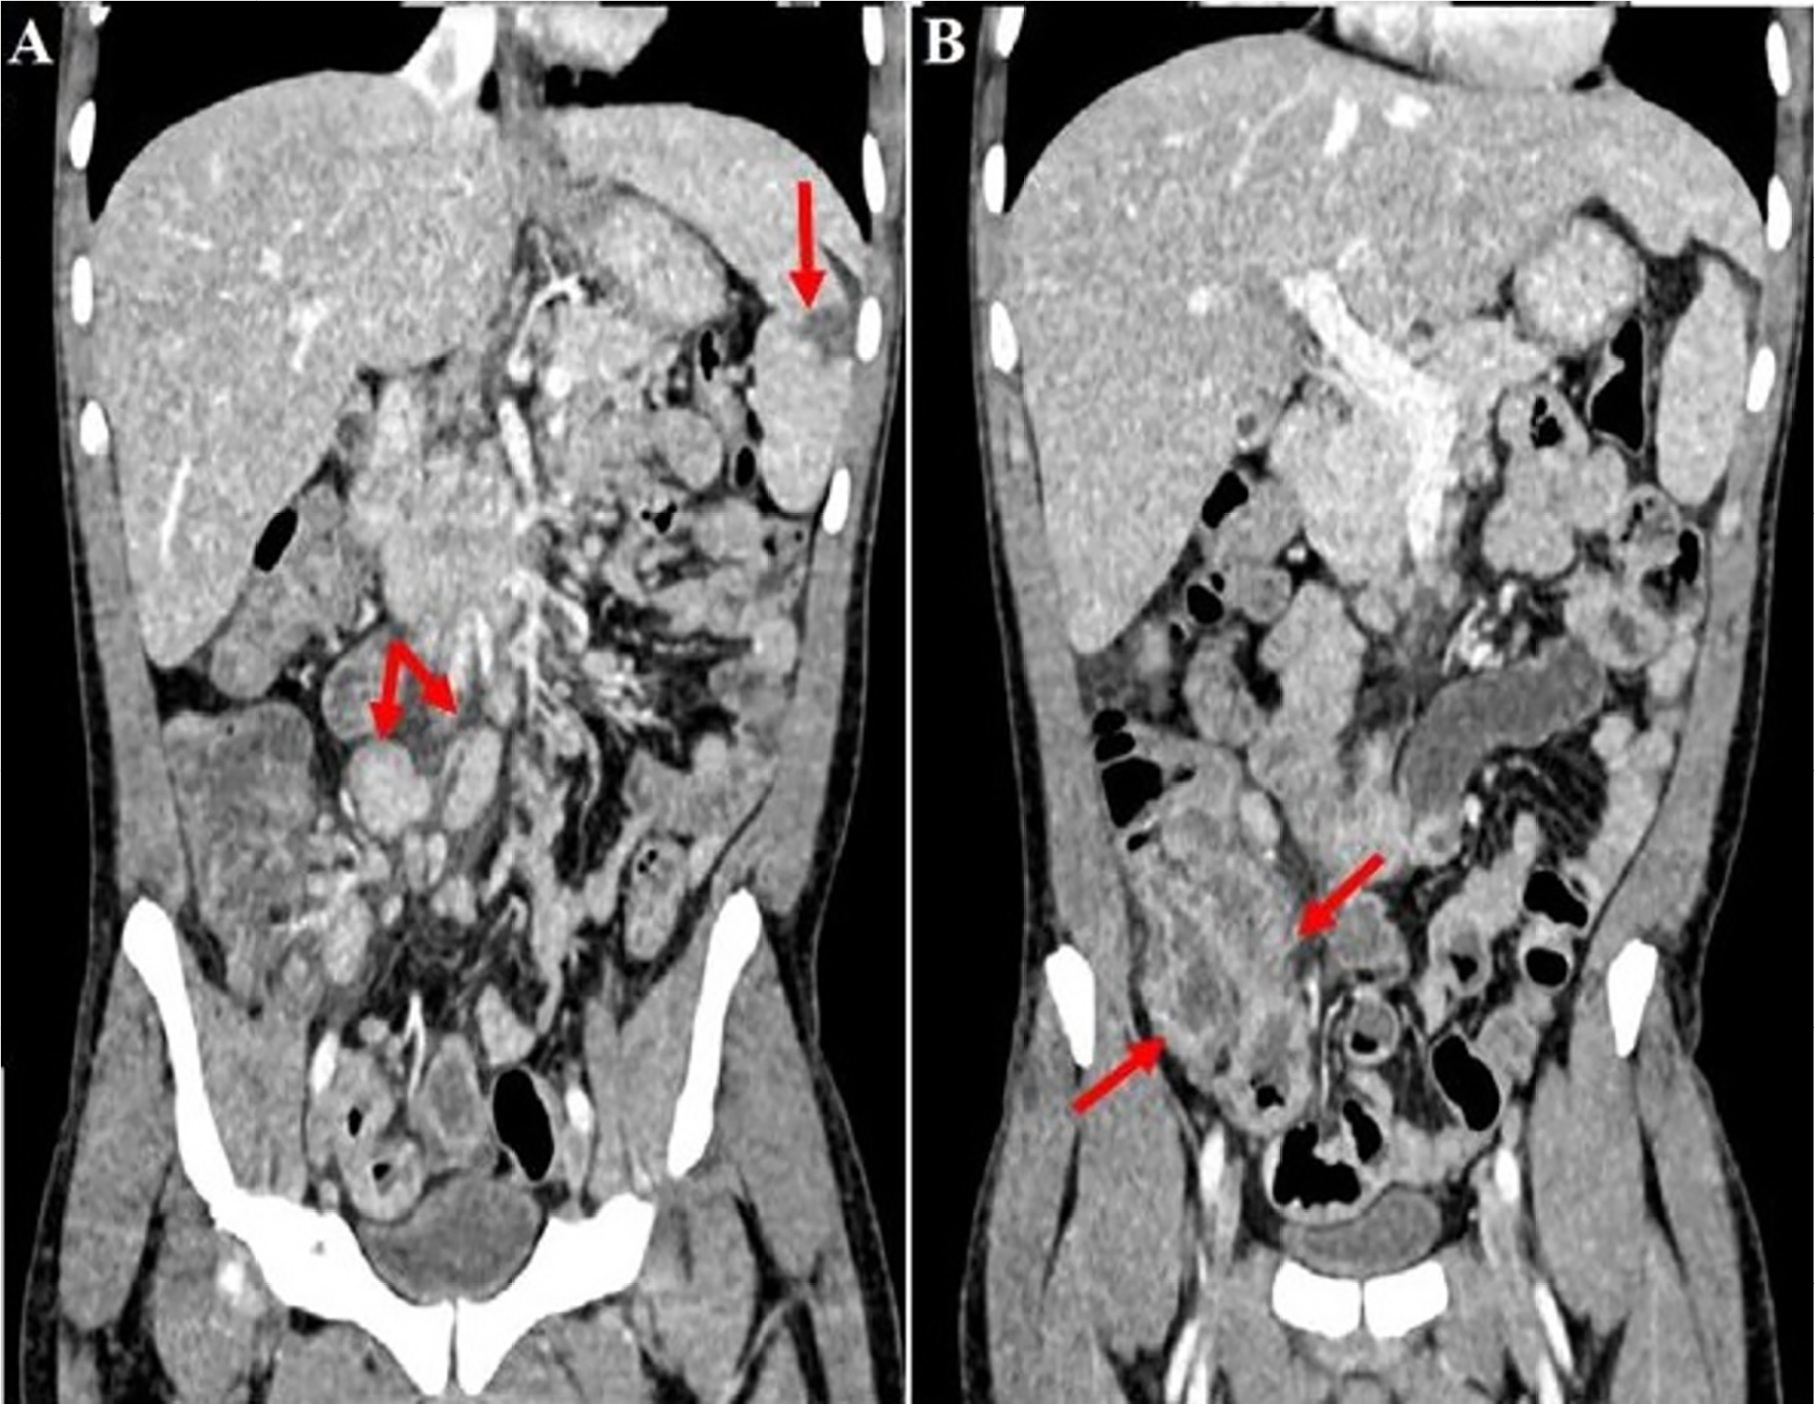

A infecção causada pela bactéria Salmonella typhi continua sendo importante preocupação para a saúde global, especialmente em regiões de acesso limitado a saneamento básico. Conhecida por sua ampla variedade de apresentações clínicas e agressividade ao provocar necrose tecidual, a febre tifoide pode representar um diagnóstico desafiador em áreas endêmicas onde outras doenças com manifestações semelhantes têm maior prevalência, o que agrava ainda mais seu potencial de morbimortalidade. Neste artigo relatamos o caso de um paciente com febre tifóide cujo diagnóstico foi inicialmente confundido com tuberculose intestinal e que evoluiu para perfuração e óbito.